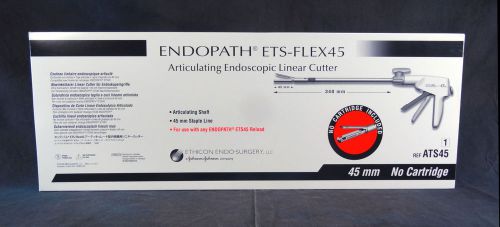

Ethicon Articulating Endoscopic Linear Cutter ATS45 - NEW EXP: 7/2019